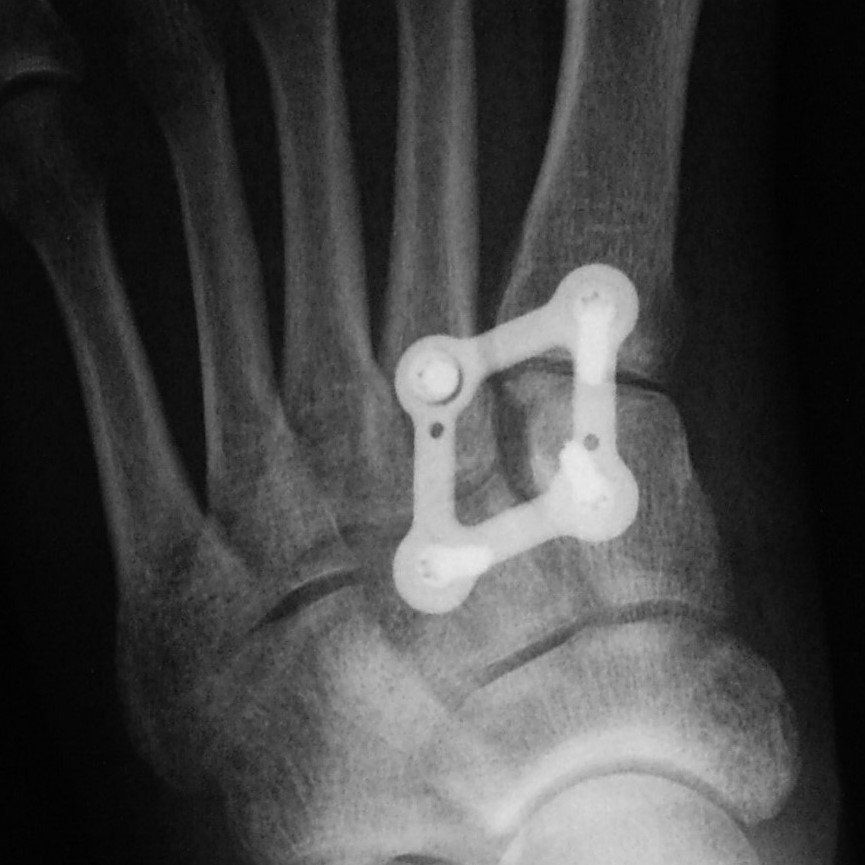

This surgical procedure involves reducing the midfoot joints and holding them stable until healing occurs.

Strong suture material (Arthrex Lisfranc Internal Brace) or a plate and screws is inserted. The pattern of injury determines what is used.

Plate fixation is stronger than suture fixation but requires plate removal 4 to 6 months after insertion.